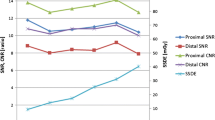

Scatter plots for image noise vs biometrical data

To test for dependencies between image noise and biometrical data several scatter plots were analysed (Figs. 3, 4, 5, 6). The slopes of the linear fits are given in Table 3. The regressions were compared to a function with slope zero using Student’s t test. The p values are given in Table 4. A p value <0.05 was considered statistically significant indicating a dependency between image noise and the biometrical parameter.

Compared to group A1 the slope of the linear fit for weight was reduced in group A2 and was nearly zero in group B (Figs. 3, 4); however, the slope of the linear fit for the BMI in group B was also reduced but still significantly different from zero (Figs. 5, 6). There was a good agreement between the results measured in the aorta and the pulmonary trunk for all patient groups indicating a homogeneous contrast media delivery.

As shown in Table 3 the linear fits of image noise vs the patients weight and the BMI are showing non-zero slopes in group A1 indicating a correlation, whereas no correlation could be found for height. As expected, the slopes for BMI and weight are positive (Figs. 3, 5) indicating growing noise levels for increasing patient weight and BMI. Since radiation dose and therefore the image noise level was chosen to be diagnostically sufficient for heavier patients, this led to a relative overexposure of low-weighted patients. In theory this could be corrected by introducing BMI or weight-adapted tube current-time settings; the latter was successfully established for CT of the chest and the abdomen [11, 13]. As BMI depends on two parameters (weight and height), weight-adapted tube current-time settings were used for this study to keep the correction directive as simple as possible.

The slopes of the linear fits for noise vs weight decreased to nearly zero indicating an improved dose distribution within the patient group A2. This was verified with a t test for a slope of zero where the patients weight and image noise were decoupled so that there was neither an overexposure for patients with low weight nor an underexposure of heavy patients. Regarding the linear adaptation a slope of zero indicating a balanced image noise can be judged as optimal; thus, the simulated dose reduction (group A2) with current-time settings equal to patients weight multiplied by four in milliampere seconds showed an optimised dose usage when compared to the standard scan protocol (group A1); however, it has to be kept in mind that the dose settings and the hereby obtained results are only valid for our particular CT scanner. But it can be assumed that the approach is transferable to other CT scanners.

True to the simulation the linear fit of image noise and weight in group B showed a slope of nearly zero (p>0.68) indicating an optimised dose distribution in this patient group; hence, the weight-adapted protocol is a practical and easy-to-handle directive for use in clinical routine.